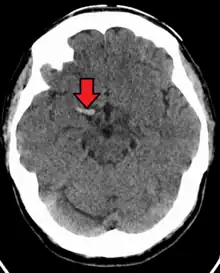

Cerebral venous sinus thrombosis (CVST) is a rare form of stroke which results from the blockage of the dural venous sinuses by a thrombus. Symptoms may include headache, abnormal vision, any of the symptoms of stroke such as weakness of the face and limbs on one side of the body and seizures. The diagnosis is usually made with a CT or MRI scan. The majority of persons affected make a full recovery. The mortality rate is 4.3%.[7]

A stroke is the rapid decline of brain function due to a disturbance in the supply of blood to the brain.[10] This can be due to ischemia, thrombus, embolus (a lodged particle) or hemorrhage (a bleed).[10] In thrombotic stroke, a thrombus (blood clot) usually forms around atherosclerotic plaques. Since blockage of the artery is gradual, the onset of symptomatic thrombotic strokes is slower. Thrombotic stroke can be divided into two categories — large vessel disease or small vessel disease. The former affects vessels such as the internal carotids, vertebral and the circle of Willis. The latter can affect smaller vessels, such as the branches of the circle of Willis.